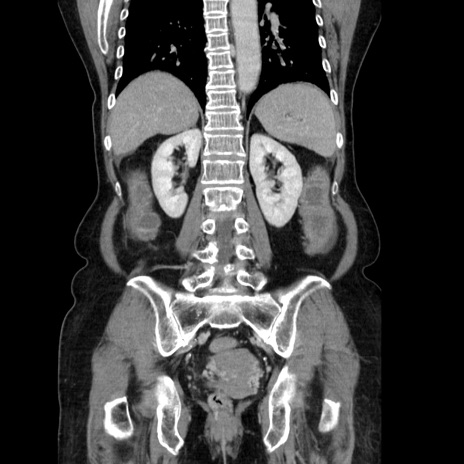

症例5(冠状断像)

【症例】70歳代女性

【主訴】お腹が張る

【現病歴】1週間くらい前から腹部膨満の自覚あり。昨日夜から増悪したため、本日救急外来受診。

【身体所見】意識清明、BT 36.5℃、BP 165/106mmHg、HR 80bpm、SpO2 98%、腹部:膨満、軟、自発痛・圧痛なし、触診にて不快感あり、腸蠕動音:減弱

【データ】WBC 12600、CRP 1.04